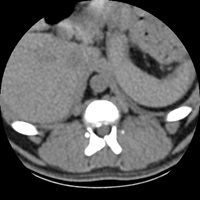

Axial Skeleton

- Suspicion of acute or chronic herniated discs

- Exploration of cervical vertebral instabilities and Wobbler's syndromes

- Traumatic assessment, exploration of vertebral fractures

- Suspicion of discospondylites (infection of discs and vertebral bodies)

- Exploration of Ponytail Syndrome

- Spinal and paraspinal tumour extension assessment